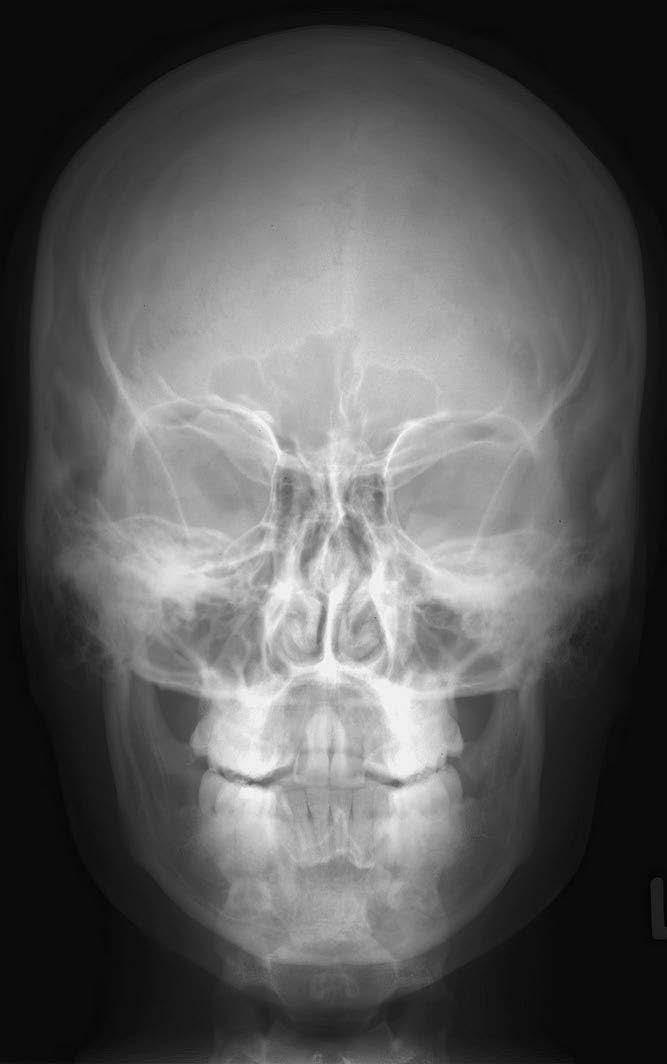

1 sutura sagittalis (šev šípový)

2 foveolae granulares

3 sutura lambdoidea (šev lambdový)

4 sinus frontalis (dutina kosti čelní)

5 strop orbity (očnice)

6 planum sphenoidale

7 cellulae ethmoidales (etmoidální sklípky / dutinky kosti čichové)

8 sutura frontozygomatica (šev mezi kostí čelní a kostí lícní)

9 horní hrana pyramidy (kosti skalní)

10 linea innominata

11 meatus acusticus internus (vnitřní zvukovod)

12 arcus zygomaticus (jařmový oblouk)

13 caput mandibulae (hlavice dolní čelisti)

14 septum nasi et concha nasalis inferior (nosní přepážka a dolní nosní skořepa)

15 sinus maxillaris (dutina horní čelisti)

16 processus mastoideus (bradavkový výběžek)

17 squama occipitalis (šupina kosti týlní)

18 dens axis (zub čepovce)

19 maxilla (horní čelist)

20 canalis mandibulae (kanál v dolní čelisti)

21 angulus mandibulae (úhel dolní čelisti)

22 mandibula (dolní čelist)

23 protuberantia mentalis (bradový výběžek)